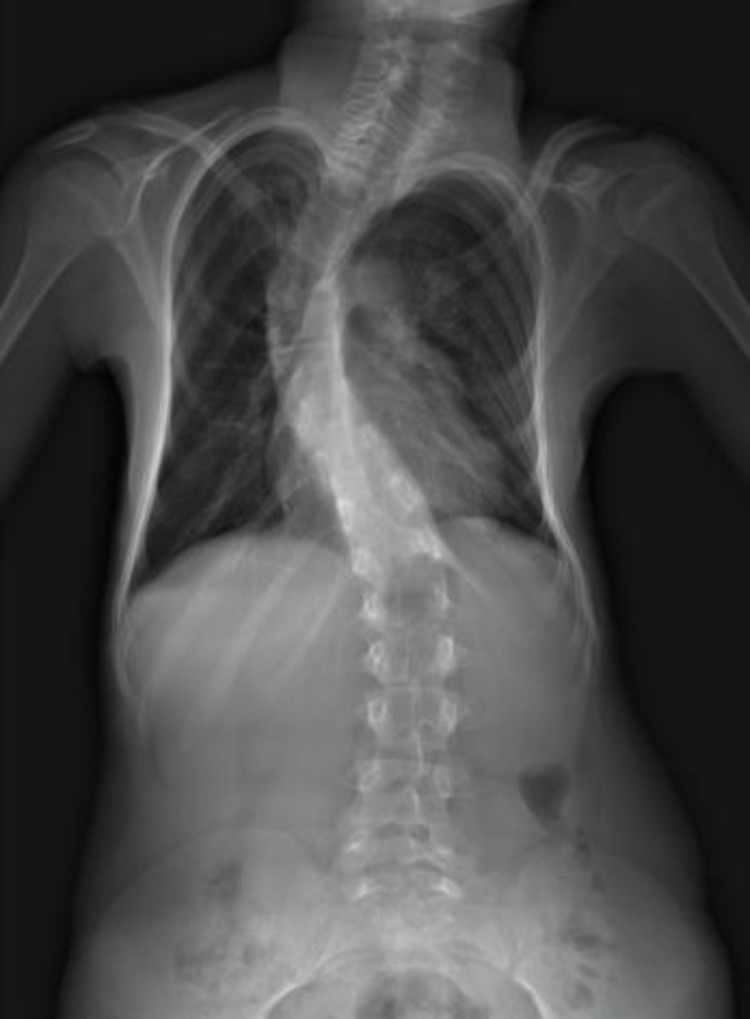

The patient had right thoracic scoliosis from Th1 vertebra to L2 vertebra. The Cobb angle in the radiograph was 55 degrees, and kyphosis of the thoracic region was 80 degrees (Figs. 3, 4). The patient’s gait was impaired as she was dragging her feet. Clinically, obvious kyphoscoliosis with the costal hump of 3 cm was seen. Her heels were in valgus deformation. Blood tests taken before the surgery showed no pathology. A whole spine MRT was performed and showed no other abnormalities except kyphoscoliosis.

Fig. 3.

Thoracic scoliosis